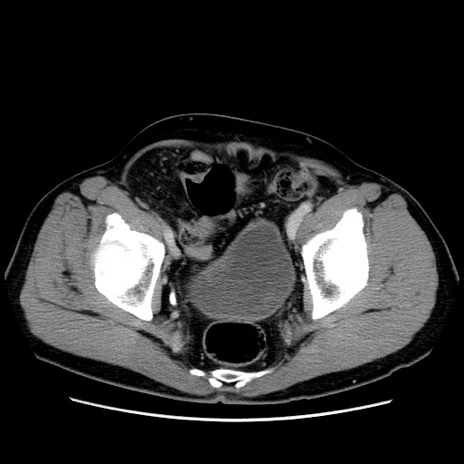

症例34(横断像)

【症例】60歳代 男性

【主訴】右鼠径部膨隆

【現病歴】1年程前より右鼠径部膨隆あり。自己にて還納可能だったため放置していた。3時間前より右鼠径部の脱出を認め、還納困難となり受診。

【身体所見】右鼠径部に小児頭大の膨隆あり。弾性硬であり、用手還納は困難。左鼠径部にも膨隆を認める。脱出はなし。